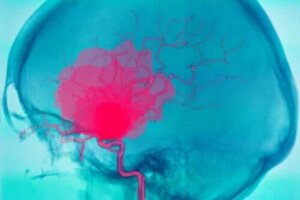

Hemoragia intracerebrală, așa cum am menționat în introducere, este sângerarea care apare în interiorul creierului. De obicei, provoacă leziuni neurologice cu debut brusc și chiar comă din cauza lipsei de aport de sânge către alte părți ale creierului. Sângele nu își continuă călătoria prin vasele de sânge. Este important să se facă distincția între hemoragia intracerebrală și cea intracraniană.

Hemoragiile intracraniene, spre deosebire de hemoragiile intracerebrale, apar în interiorul craniului, dar nu în parenchimul creierului: de exemplu, hemoragiile intraventriculare, subarahnoidiene, subdurale și epidurale.

Hemoragia intracerebrală este una dintre principalele cauze ale accidentului vascular cerebral. De fapt, experții estimează că aproape 15% din accidentele vasculare cerebrale sunt cauzate de această afecțiune. În plus, are o rată ridicată a mortalității, mai ales în primele zile.